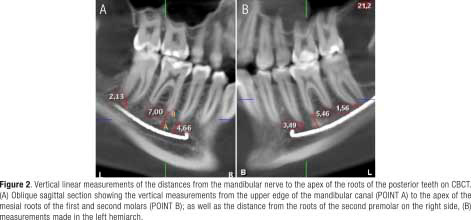

The lower occlusal plane was leveled to the floor in the cross-section, and the panoramic reformation was performed using the “Manual panoramic” tool. Points were then placed following the path of the mandibular canal using the “Draw Nerve” tool. The position of the mandibular canal and the apices was assessed in the oblique sagittal view, with an interval of 1mm (Figure 1). The vertical distance from the upper edge of this canal (POINT A) to the apex of the mesial roots of the first molars and second molars (POINT B) was measured in oblique sagittal sections, as well as the distance from the roots of the second premolars that presented a single root in the right and left hemiarch in men and women, using Planmeca Romexis®5.3.3.3 software (Figure 2) (21). The data were entered into a data collection form, where each tomography measurement was recorded by means of codes, with the following recorded: sex, age, hemiarch, and the vertical distance of each root apex of the first molars, second molars, and second premolars. Planmeca Romexis® 5.3.3.5 software and iMac MXWT2LL/A (Apple brand with an Intel Core i5-6700K processor with 8 GB of RAM memory and 256 GB of SSD) were used to perform the respective measurements.